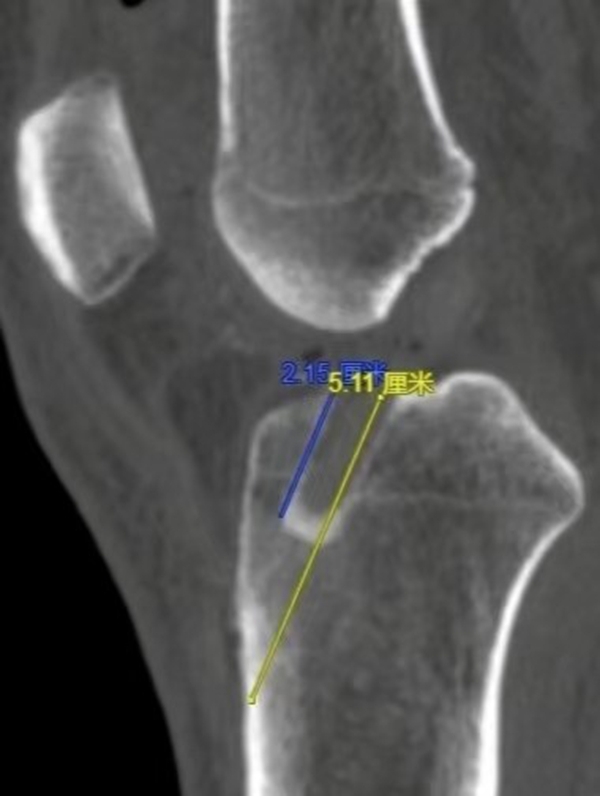

传统重建方法胫骨端的骨道为全骨道,长度约5cm左右(黄色线条),而全内重建胫骨端仅需要关节腔侧长约2.5cm左右的骨道(蓝色线条),保留了更多的骨质(图4/图5)。

图 5 全内重建术后胫骨骨道